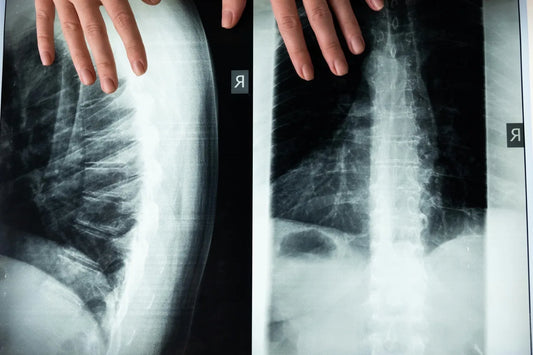

Testosteron stabilisiert die Knochenstruktur

Ein ausgeglichener Testosteronspiegel trägt zur Förderung der Knochendichte bei und kann somit das Risiko von Osteoporose (Knochenschwund) verringern (Fink et al., 2006). Das Hormon wirkt direkt auf die Knochenzellen und beeinflusst den Mineralstoffwechsel, um die Knochengesundheit zu unterstützen.

- Knochendichteverlust: Ein niedriger Testosteronspiegel kann zu einer verminderten Knochendichte und einem erhöhten Risiko für Osteoporose führen (Fink et al., 2006).

Ein akuter Testosteronmangel lässt sich auch durch sichtbare Veränderungen am männlichen Körper erkennen. Wird zu wenig von dem Hormon produziert, kann es zu einem rapiden Abbau von Muskelgewebe und einer Zunahme von Körperfett kommen. Ein Ungleichgewicht zwischen Testosteron und Östrogen sorgt bei Männern für eine Anlagerung von Körperfett, besonders im Bauchbereich. Außerdem besteht ein erhöhtes Risiko für Knochenbrüche und Osteoporose(Knochenschwund) (Shigehara et al., 2021).